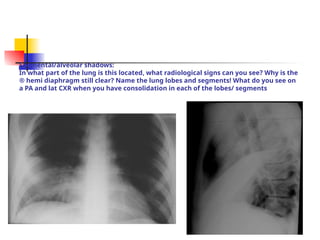

Segmental/alveolar shadows:

In what part of the lung is this located, what radiological signs can you see? Why is the

® hemi diaphragm still clear? Name the lung lobes and segments! What do you see on

a PA and lat CXR when you have consolidation in each of the lobes/ segments